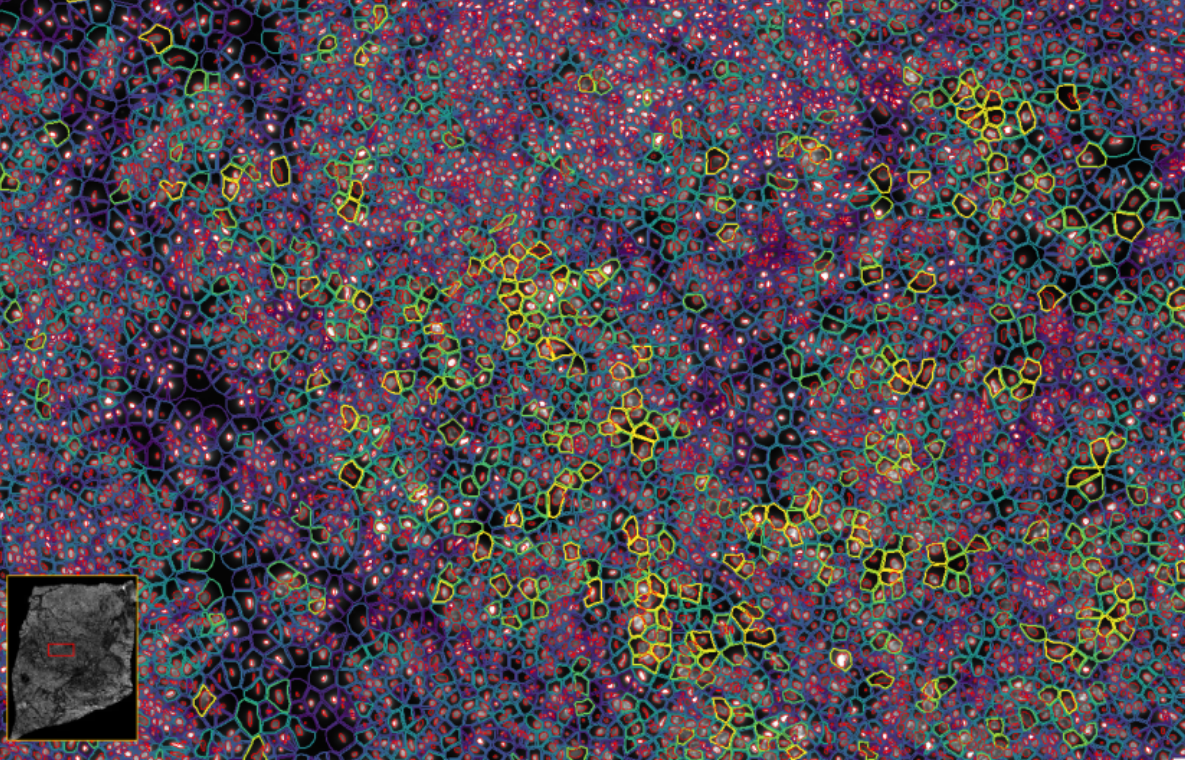

image.png

ͼ3£ºXenium½«¹âÑ§ÌØÕ÷½âÂëΪת¼±¾±í´ï£¬£¬£¬£¬£¬ÊÕÂÞ²¢ÐγÉͼÏñ

ͼ4-1£ºÊ¹ÓÃDAPI¶Ôϸ°ûºËȾɫ£¬£¬£¬£¬£¬ÍŽáÉî¶ÈѧϰҪÁìÍÆ¶ÏÍêÕûµÄϸ°û½çÏß